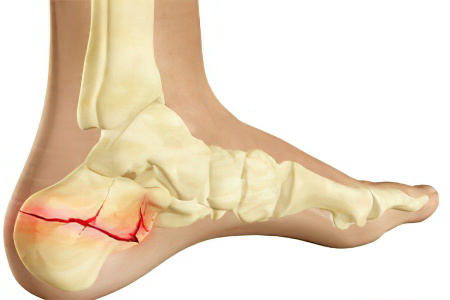

Наиболее распространённые причины болей в области пятки — натирания от обуви и серьёзные травмы, такие как ушибы, трещины и переломы пяточной кости. Почти каждый из нас хотя бы раз сталкивался с ситуацией, когда неудачно ударялся ногой, например, не рассчитал расстояние до препятствия позади себя. В некоторых случаях врачи диагностируют пяточные бурситы и растяжения ахиллова сухожилия. Менее распространённым заболеванием является деформация Хаглунда — костно-хрящевой нарост на пятке, который образуется в задней верхней части и вызывает дискомфорт при ходьбе, а также усложняет выбор подходящей обуви.

Боль в боковых поверхностях пяток

Боль во внутренней части пятки чаще всего возникает из-за растяжения медиальных связок голеностопного сустава, что происходит при вывихе стопы наружу. Если же боль локализуется на внешней боковой стороне пятки, это может указывать на вывих ноги внутрь. Также причиной дискомфорта могут быть ушибы, трещины или переломы. В большинстве случаев проблема имеет травматическую природу, и игнорировать её нельзя из-за интенсивной боли и отека.

Перелом пяточной кости считается одним из самых сложных видов травм. Он часто сопровождается смещением осколков, разрывом связок и сухожилий. Лечение требует тщательной иммобилизации конечности, а процесс заживления занимает от 3 до 4 месяцев. В этот период пациенту запрещено наступать на поврежденную пятку.